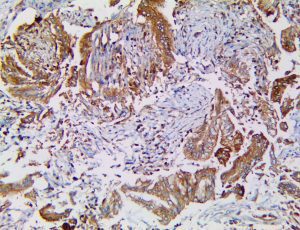

The first cytokines released are interleukin 1β (IL-1β) and tumor necrosis factor-α (TNF-α), which attract a variety of circulating white blood cells (WBCs) to the infection site, including neutrophils, monocytes, macrophages, and natural killer (NK) cells. This response, along with the antipathogenic chemicals released by these cells (i.e., complement), comprise the innate immune response. These cells directly attack the invading pathogen and also release additional cytokines, chief among them interleukin-1 and 6 (IL-6). IL-6 is essential for invoking the adaptive immune response, which calls T-cells, B-cells, and T helper (Th) cells to the infection site. IL-6 also stimulates further recruitment, proliferation and activation of macrophages.

This activation induces inflammatory monocytes to highly express IL-6, starting a localized and then systemic cascade effect that results in hyperproduction of IL-6, which accelerates the inflammatory process. Because IL-6 also increases vascular permeability, excessive levels cause blood vessels to become very leaky. This, along with clotting factors released from vascular endothelial cells, stimulates the coagulation cascade, resulting in microthrombosis (tiny clots), which leads to ischemia and tissue death of the kidney, intestines, heart, liver, brain and extremities.